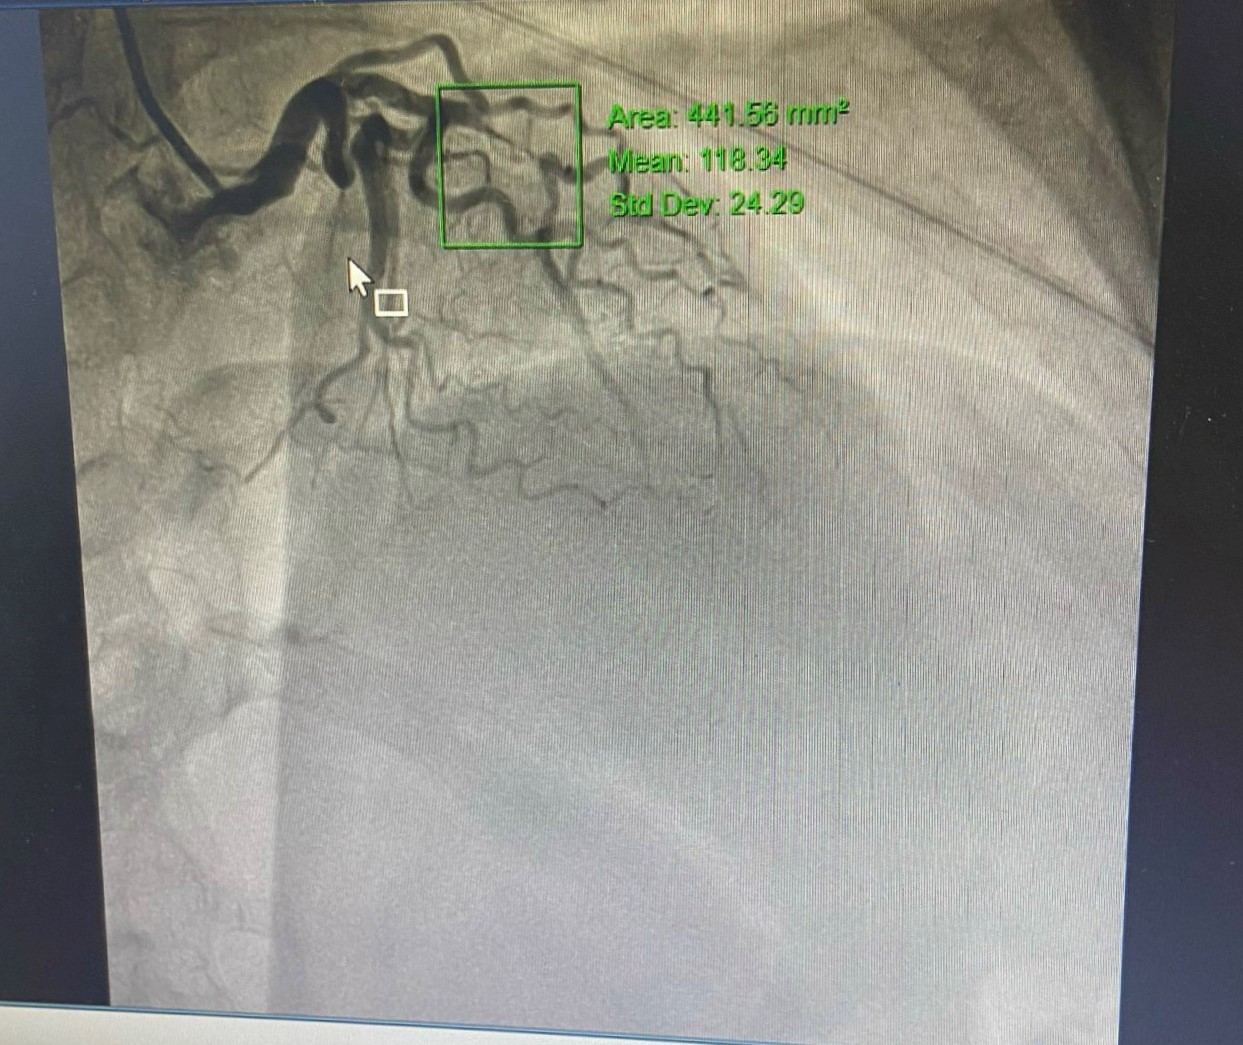

Kết quả chụp mạch vành cho thấy, hẹp 99% động mạch liên thất trước LAD I-II. Ngay lập tức, bệnh nhân được kíp Ths.BSNT Vũ Học Huấn – Trưởng Khoa Tim mạch – Đột quỵ, Ths.BS Phạm Văn Thuận cùng cộng sự thực hiện kỹ thuật can thiệp đặt 1stent mạch vành. Nhờ được phát hiện, can thiệp cấp cứu kịp thời mà bệnh nhân đã thoát khỏi giai đoạn nguy hiểm, đang dần phục hồi. Ghi nhận kỹ thuật đạt kết quả tốt.